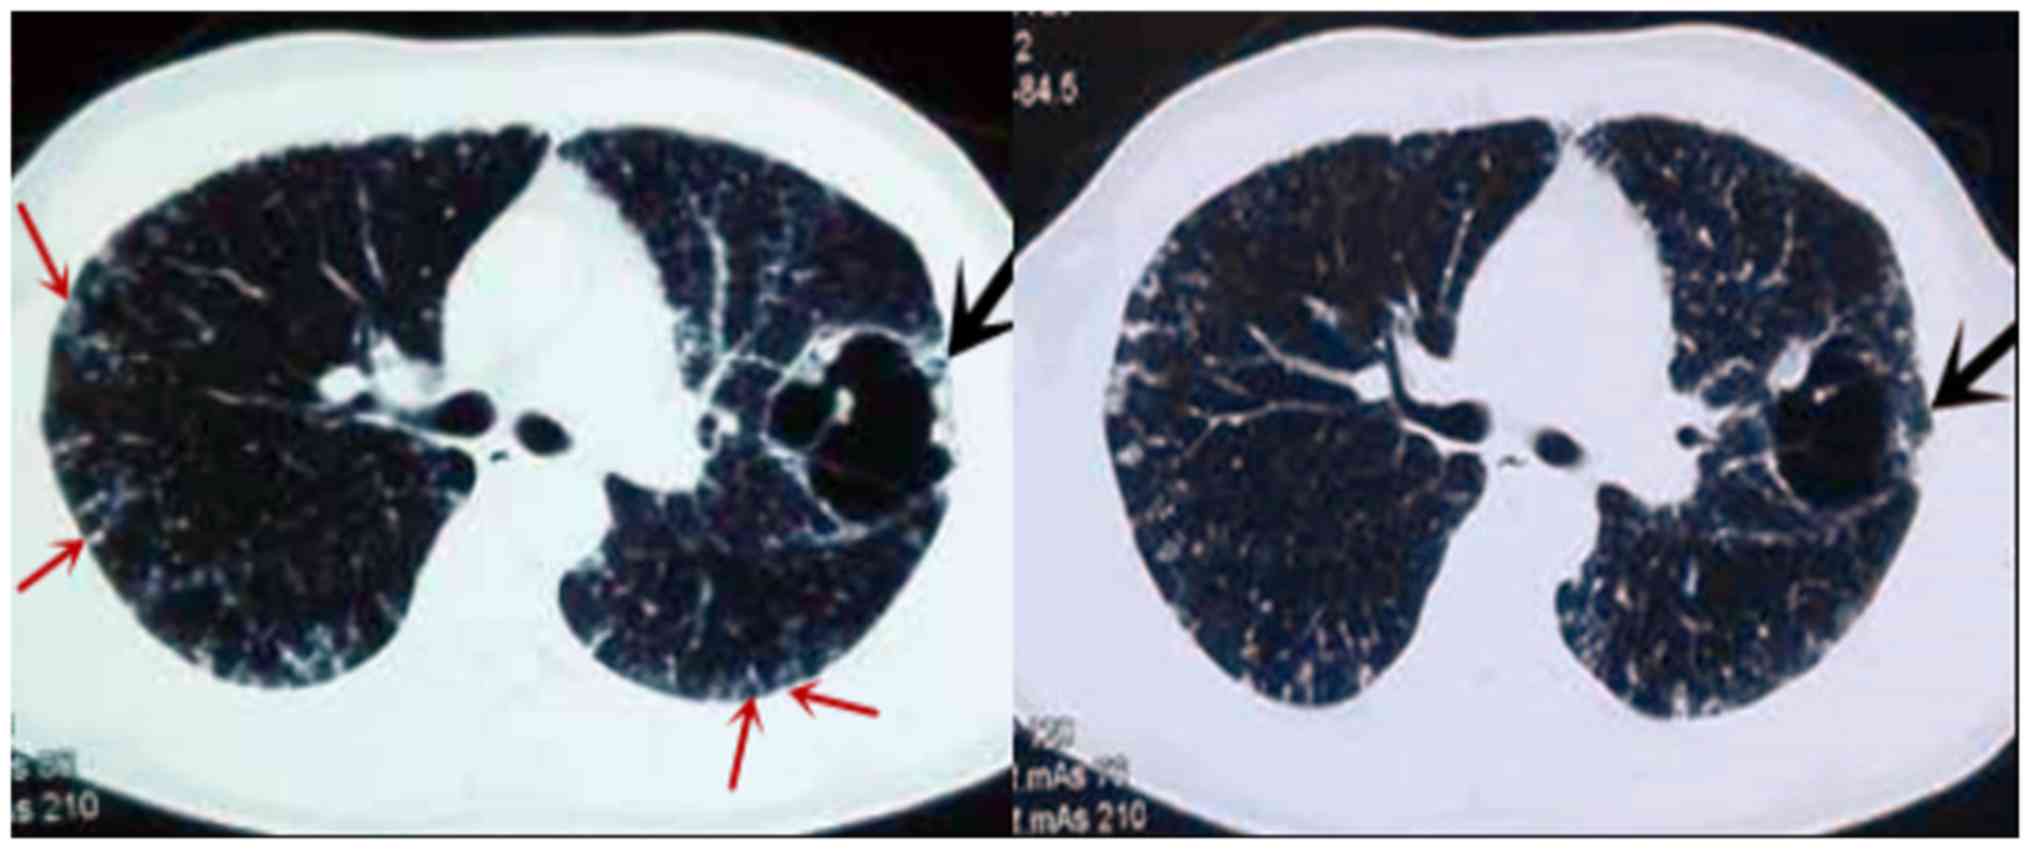

Fig. 1 demonstrates CT manifestations of thin-wall cystic lung cancer. The primary lesions occurred at the right lower lobe in 14 patients, at the right middle lobe in 5 patients, at the right upper lobe in 4 patients, at the left upper lobe in 10 patients, and at the left lower lobe in 12 patients. The wall thickness of cysts ranged between 1 and 4 mm. Each of them displayed one or more suspected malignant signs of lung cancer, including asymmetric thickening (96.8%), separation in cysts (54.8%), irregular margin (51.6%), small spicules (35.5%), dragging sensation in the pleura (22.6%), lobulation (19.3%) and ground-glass opacity (9.6%).

One 33-year-old patient with a 2-month history of cough and sputum presented with a large, abnormal cystic lesion in the left lung and multiple cystic lesions in the two lungs on CT images (Fig. 3). The diagnosis by CT and PET/CT was pulmonary bullae. Pleural involvement, repeated pneumothorax and choking sensations in the chest were evident. Due to these signs, the possibility of malignant lesions was not ruled out. Therefore, bronchoscopic biopsy was performed, which confirmed these cystic lesions as intrapulmonary metastatic adenocarcinoma.

Thin-wall cystic lung cancer is most common in adenocarcinomas. Xue et al (11) reported that thin-wall cystic lesions were detected in 15/18 patients with moderately- or well-differentiated adenocarcinoma. Qi et al (12) also reported 16 cases of adenocarcinoma. In the present study, a 57-year-old man presented with primary thin-wall cystic squamous cell carcinoma. Initially he was diagnosed with tuberculosis cysts, but a bronchoscopic biopsy identified it as poorly-differentiated squamous cell carcinoma. The lesion displayed the suspected malignant signs of lung cancer, including asymmetric thickening of the wall, short spicules, lobulation and irregular margins. However, no necrosis was observed inside the lesion. This case indicates that thin-wall cystic lesions are not limited to adenocarcinoma.